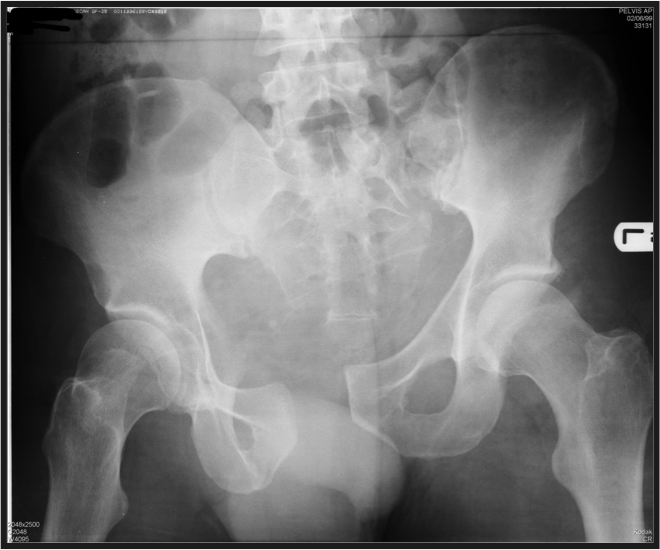

malgaigne fracture

(the penis points the the pathology)